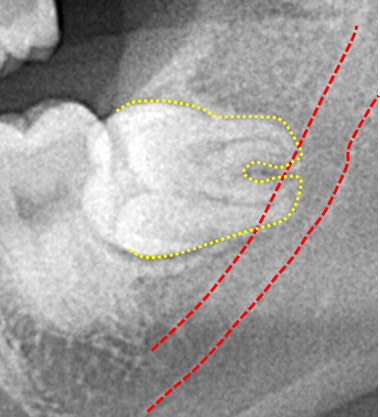

パノラマレントゲン撮影で得られる画像は2次元のため、下顎神経の走行や上顎洞と歯の詳細な位置関係を知るのが難しい場合があります。

CT像では歯の生え方や神経の走行、上顎洞との位置関係などを3次元で確認することができるため、より正確な診断が可能です。主治医が総合的に判断しCT撮影を提案された場合はより安全な抜歯のために受けることをお勧めいたします。また患者様のご希望でも撮影は行いますのでお申しつけください。

親知らずの歯根の先端と下顎神経が近接している場合は2回に分けて抜歯を行うことがあります。まず、親知らずを2分割して頭の部分を抜きます。その後しばらく期間をおいて、のこる歯根の部分が頭を抜いたスペースに移動したのを確認して抜きます。

このように2回に分ける事で安全な抜歯が可能です。

歯冠切除量と歯根の移動量の結果です。術前の智歯(親知らず)の幅径に対して計測した智歯の長径の割合は1.21ポイント、術後は1.10ポイントで有意に差を認めました。数ヵ月待機することにより歯根は有意に近心側に移動していることを認めました。